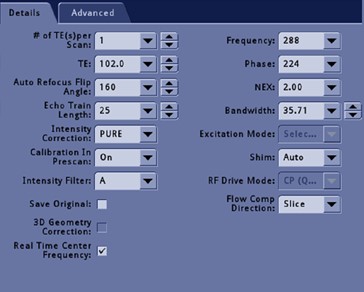

Real Time Center Frequency

The Real Time Center Frequency option is available with DW-EPI scans, DTI scans (DW-EPI scans with Tensor selected as the Diffusion direction) and 2D FSE Fat SAT scans (2D FSE with Fat Saturation). In DW-EPI and DTI scans, Real Time Center Frequency applies the optimal center frequency for each slice. In 2D FSE Fat SAT scans, when the option selected on, dynamic center frequency and shim will be applied for each prescribed slice to improve fat saturation performance.

The Real Time Center Frequency option is located on the Details tab for DWI and DTI scan prescriptions.